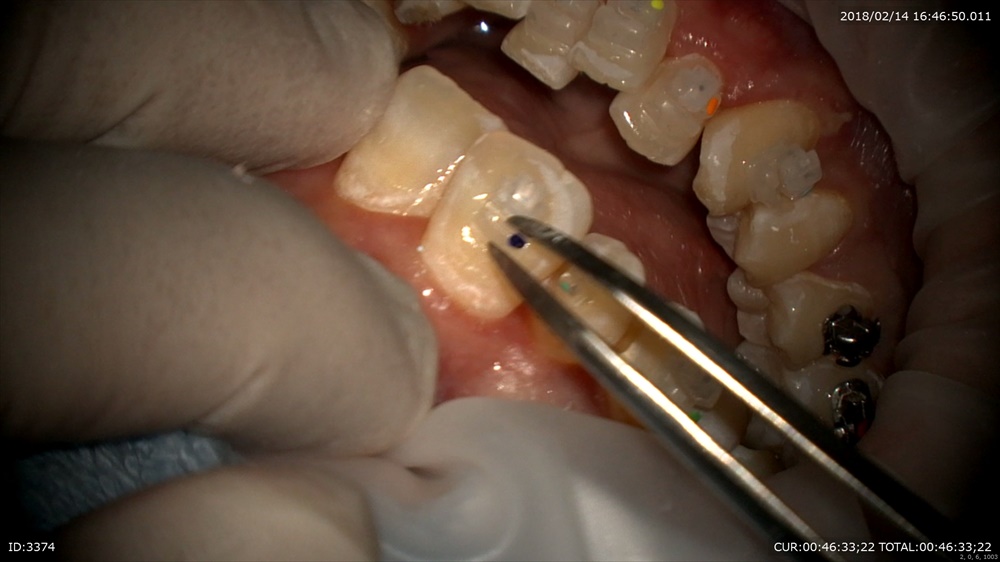

次の方は精密根管治療が終了しかぶせ物の型取り。

仮歯を外して

型取り

写真を撮ってどれがかぶせ物かわからないようにオーダーメイドへ。セラミスト間中先生の出番。